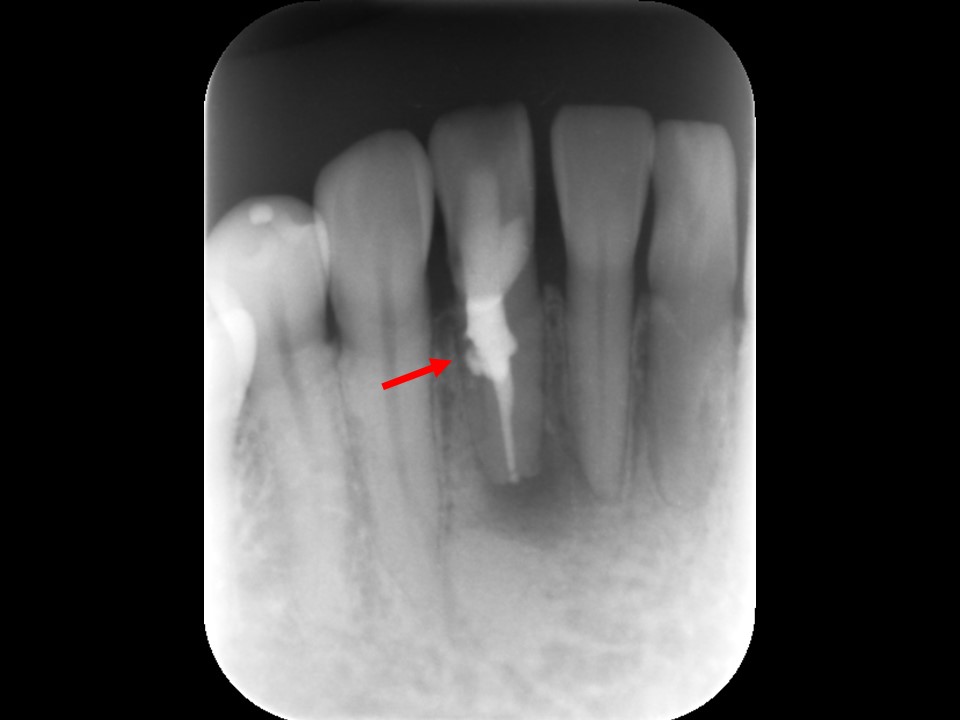

治療前のレントゲンおよびCT画像です。当該歯はすでに根管治療が施してあり、根尖部には根尖病変によるX線透過像を認めます。

また、根尖部にはファイルと思われる器具の残存を認めます(矢印)。

ガッタパーチャを除去したところです。CT画像にて根尖部に破折しているファイルが残っているのが確認できます(矢印)。

レントゲン画像上で破折したファイルが無くなっていることを確認しました。除去した長さ2mmほどのファイル破折片です。ファイルが除去できたことによって、根管内を完全に清掃・消毒を行うことが可能となります。